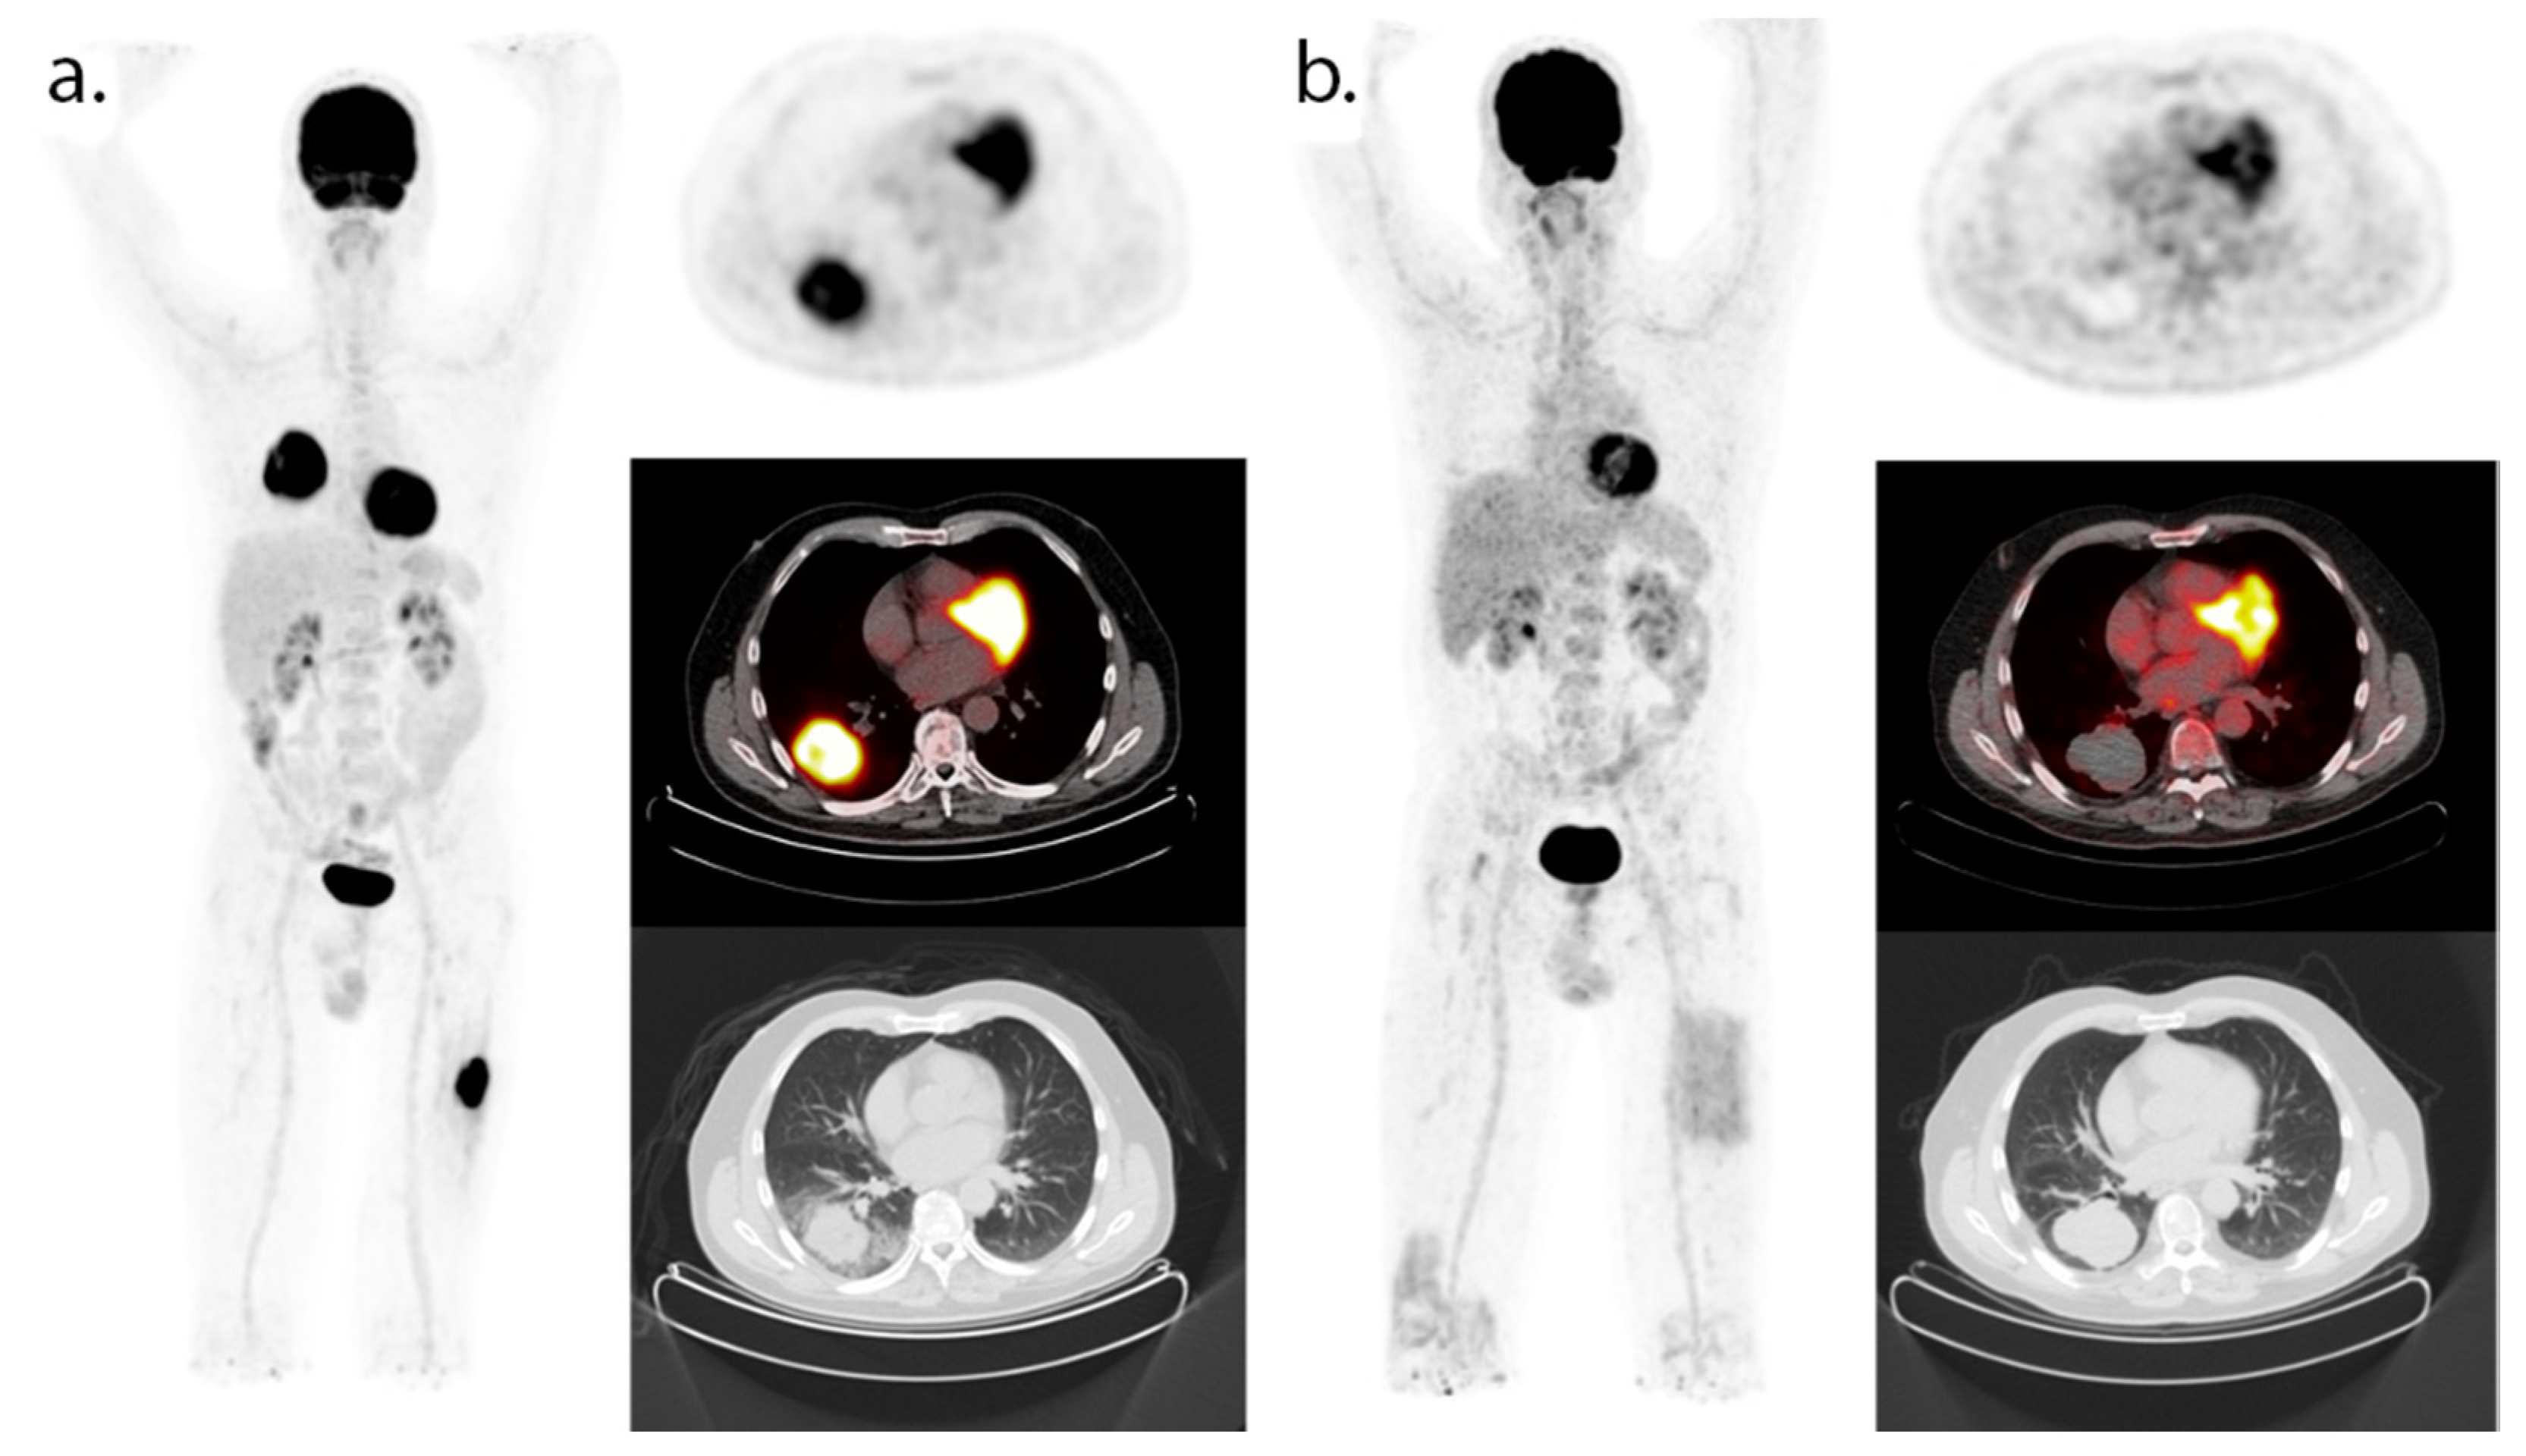

- Seith, F.; Forschner, A.; Schmidt, H.; Pfannenberg, C.; Gückel, B.; Nikolaou, K.; La Fougère, C.; Garbe, C.; Schwenzer, N. 18F-FDG-PET detects complete response to PD1-therapy in melanoma patients two weeks after therapy start. Eur. J. Nucl. Med. Mol. Imaging 2018, 45, 95–101. [Google Scholar] [CrossRef] [PubMed]

- Humbert, O.; Cadour, N.; Paquet, M.; Schiappa, R.; Poudenx, M.; Chardin, D.; Borchiellini, D.; Benisvy, D.; Ouvrier, M.J.; Zwarthoed, C.; et al. 18FDG PET/CT in the early assessment of non-small cell lung cancer response to immunotherapy: Frequency and clinical significance of atypical evolutive patterns. Eur. J. Nucl. Med. Mol. Imaging 2019, 47, 1158–1167. [Google Scholar] [CrossRef]